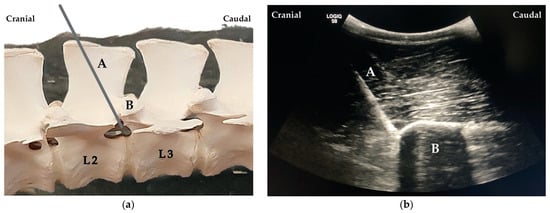

When proper needle position was achieved, the stylet was removed, and a 20 mL syringe was attached. The solution was injected (one single injection) at the site where the spinal nerve was expected to exit the intervertebral foramen. The process was repeated for L1 and L2 always taking, as reference, the visualisation of the articular process of the vertebra L1 and L2, respectively (Figure 4).

Figure 4. (a) Needle (A) placement cranial to the articular process of the second lumbar (L2) vertebra (B). (b) Ultrasound image showing the needle (A) cranially to the articular process of the vertebra L2 (B).